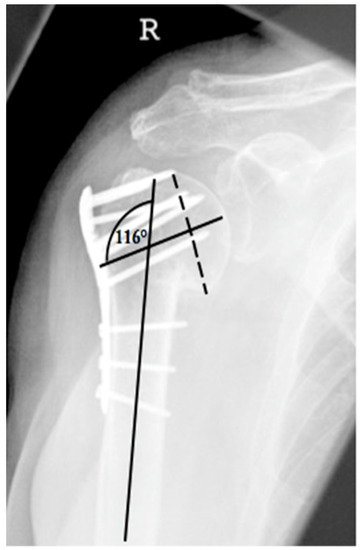

| Complication Type | Exemplary Images by X-rays or Pattern Images | Definition |

|---|---|---|

| 2c | ![]() | Type 2c is defined by a severe varus displacement (>20°) of the humeral head, which is associated with a screw cutout at the humeral head in parallel to Type 2a. In contrast to Type 2a, this varus displacement is characterized by an unstable osteosynthesis situation and progression. |

- primary unsuccessful surgical reduction (>5° head–shaft displacement, cranialization of the greater tuberosity of >5 mm and valgus head–shaft alignment >150° or <110° head shaft angle according to Schnetzke et al., 2016) [20].